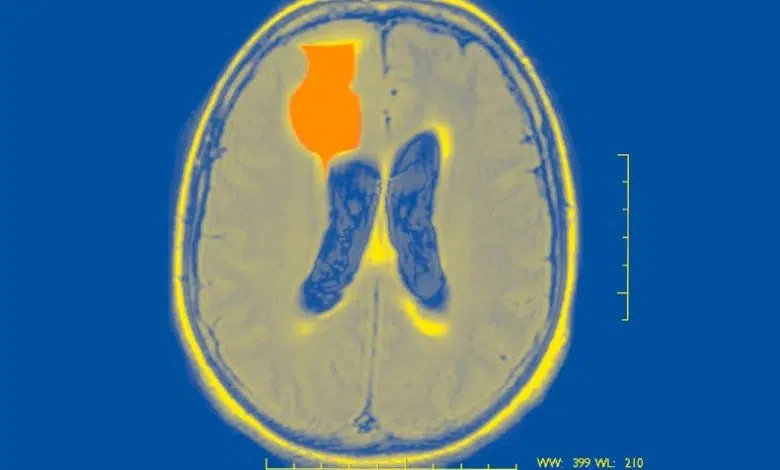

Las convulsiones son como tormentas en el cerebro: ráfagas repentinas de actividad eléctrica anormal que pueden causar alteraciones en el movimiento, el comportamiento, los sentimientos y la conciencia. Para las personas con epilepsia, no saber cuándo ocurrirá su próxima convulsión puede ser psicológicamente debilitante. Los médicos no tienen forma de decirle a las personas con epilepsia si es probable que ocurra una convulsión dentro de cinco minutos, dentro de cinco semanas o dentro de cinco meses, dice Vikram Rao, neurólogo de la Universidad de California en San Francisco. “Eso deja a la gente en un estado de incertidumbre inminente”.

En 2018, Rao y sus colegas informaron sobre el descubrimiento de ritmos cerebrales asociados con convulsiones a largo plazo, más comúnmente en el rango de 20 a 30 días, a los que denominaron ritmos «multidien» (multidía). Al examinar estos ritmos en la actividad cerebral, el grupo ahora ha demostrado que las convulsiones se pueden pronosticar con 24 horas de anticipación y, en algunos pacientes, hasta tres días antes. Sus hallazgos, publicados el 17 de diciembre en la Neurología de lanceta, elevar la posibilidad de eventualmente proporcionar a los pacientes con epilepsia pronósticos de crisis que podrían predecir la probabilidad de que ocurra una con días de anticipación.

En su último estudio, el grupo de Rao realizó un análisis retrospectivo de los datos recopilados durante un ensayo clínico de nueve años con participantes que tenían un dispositivo de neuroestimulación implantado aprobado por la Administración de Alimentos y Medicamentos, NeuroPace, que usa un tipo de electroencefalograma (EEG) para monitorear tanto convulsiones como descargas epileptiformes interictales: picos patológicos en la actividad cerebral que ocurren entre convulsiones. (Uno de los autores del estudio, Thomas Tcheng, es el director principal de investigación preclínica de NeuroPace).

Usando datos sobre el momento de las descargas epileptiformes interictales y las convulsiones pasadas, el equipo desarrolló un modelo computacional que estimó si un paciente estaba o no en riesgo de sufrir una convulsión en las horas o días posteriores. Maxime Baud, epileptólogo de la Universidad de Berna en Suiza y coautor del estudio, explica que los investigadores no estaban tratando de predecir cuándo ocurrirá exactamente la próxima convulsión, sino más bien de identificar la probabilidad de que ocurra una convulsión. durante un período de tiempo determinado, similar a cómo los pronósticos meteorológicos proporcionan un porcentaje de la probabilidad de lluvia o sol en un día determinado.

Cuando los investigadores compararon sus pronósticos con la ocurrencia real de convulsiones en 18 participantes, encontraron que en 15 de ellos (83 por ciento), el algoritmo funcionó mejor que el azar para predecir convulsiones con 24 horas de anticipación. En dos de los pacientes (11 por ciento), fue capaz de pronosticar convulsiones hasta con tres días de anticipación. Para validar aún más el modelo, el equipo lo aplicó a otro conjunto de datos más grande con 157 participantes, esta vez, evaluando si el algoritmo podía pronosticar convulsiones autoinformadas, que son la herramienta principal utilizada para la evaluación en la clínica. Los investigadores encontraron que podía pronosticar convulsiones durante 24 horas en 103 participantes (66 por ciento) y hasta tres días antes en 61 (39 por ciento). En general, las posibilidades de una convulsión eran más altas durante los períodos en que los ciclos circadianos y multidien de actividad cerebral estaban cerca de su punto máximo.